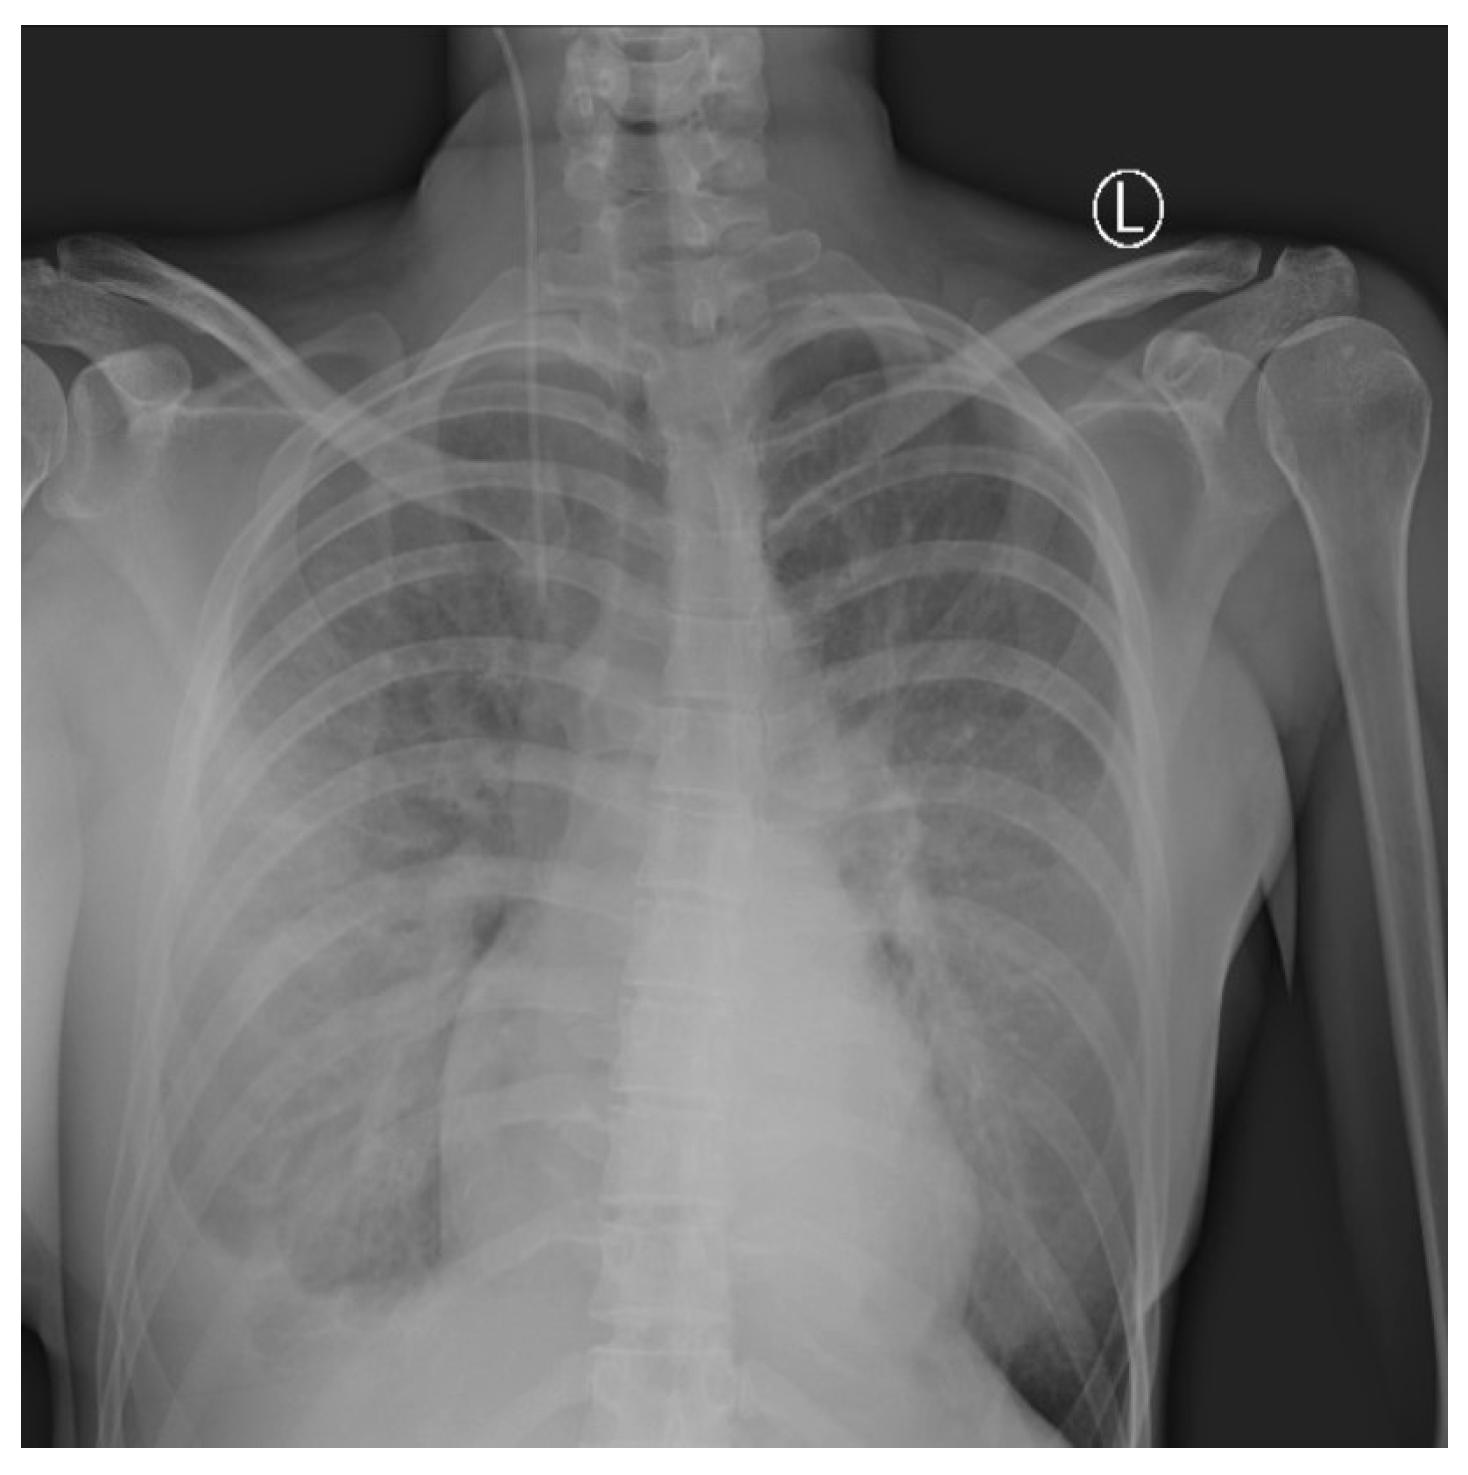

2. Case Report